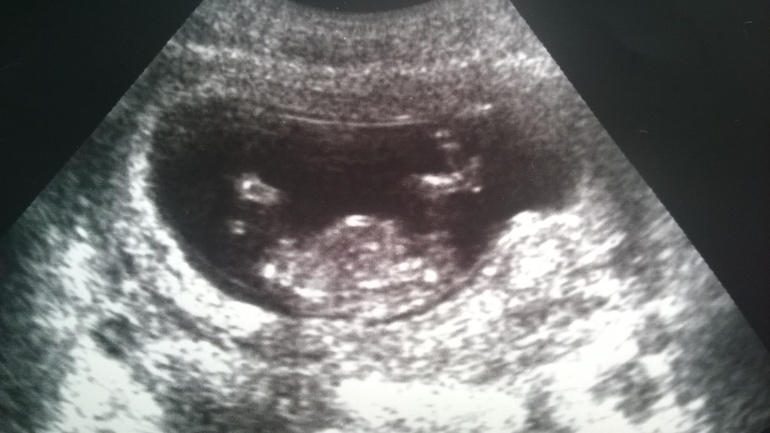

наш первый скрининг)))

Результаты: УЗИ, КТГ, доплера, скринингасегодня у нас 13 недель)( по месячным) и нас отправили на скрининг...волновалась, но оказалось что зря) ктр-5,88, твп-2,2 мм, днкп-2,1мм, все органы на месте и хорошо работают) надеялась хоть на предположение пола, но нет, узистка не смогла разглядеть) зато ее позабавило положение малыша)))этот карапуз закинул ногу на ногу и лежит довольный))) прозвали его королем)) после смеялись всем кабинетом)))